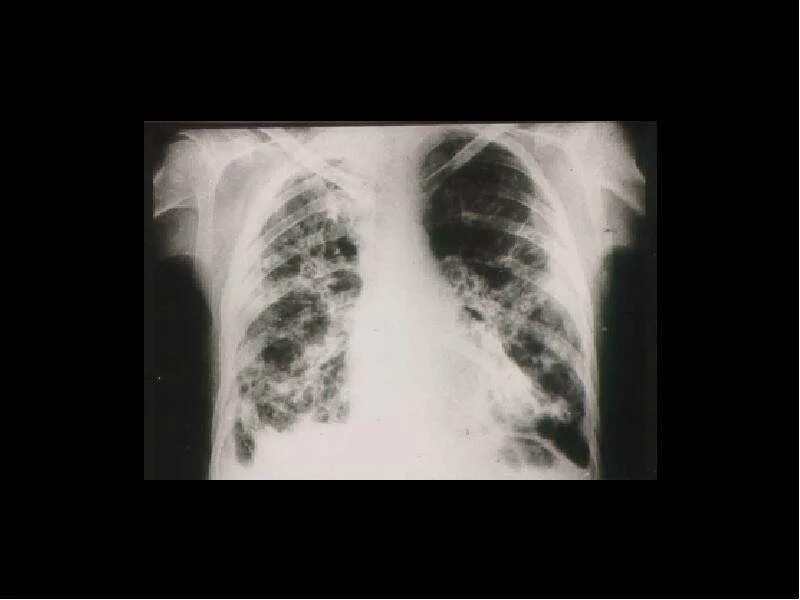

Пневмосклероз легких что это такое симптомы лечение